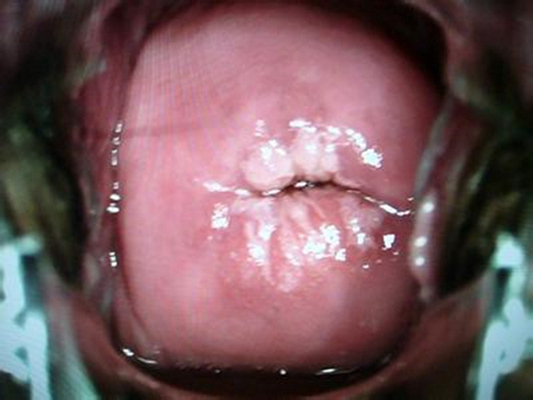

子宮頸炎圖片

宮頸炎